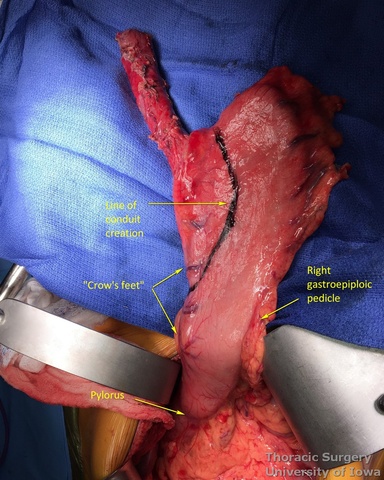

- At approximately the level of the third large vein (accompanying vagal “crow’s foot”) along the lesser curvature, lymphatic tissue and vessels are mobilized and divided to expose the gastric wall.

- Starting from the lesser curvature of the stomach, several stapler loads are sequentially fired towards the fundus of the stomach, thus creating a 4–5 cm wide gastric conduit and ensuring a 5 cm margin distal to the tumor. Depending on the thickness of the stomach, medium purple or thick black (alternatively blue or green, depending on manufacturer) loads are used.